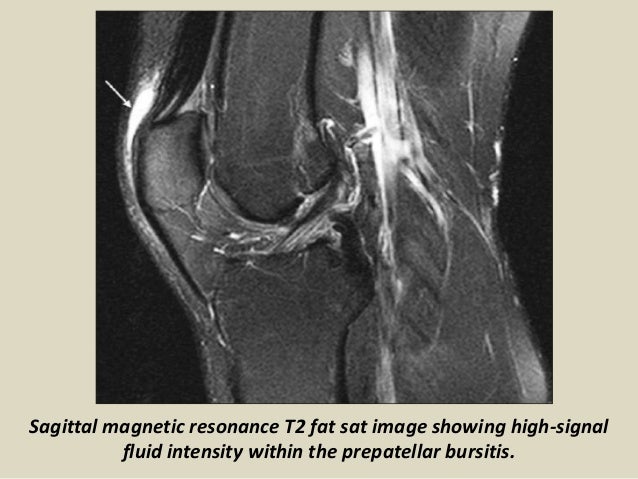

Does knee bursitis show up on MRI?

On MRI, prepatellar bursitis appears as an oval fluid-signal-intensity lesion between the subcutaneous tissue and the patella [Figure 1].